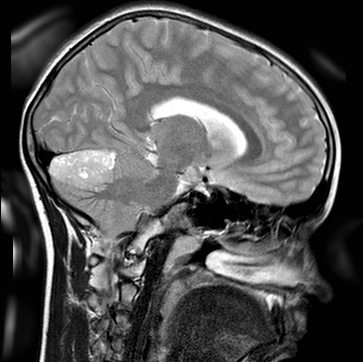

Рак головного мозга у детей – это злокачественная опухоль, которая развивается из клеток мозговой ткани. Ему характерно инфильтрационный рост (врастание патологически измененных клеток в близлежащие ткани органа) и образование метастазов (распространение мутированных клеток по всему организму через лимфатические и кровеносные сосуды).

ІІ. Медуллобластома.

Медуллобластома – это злокачественная опухоль с очень быстрым процессом роста. Новообразование развивается из тканей мозжечка. Опухоль преимущественно поражает мальчиков в возрасте 4-9 лет. Медуллобластическое новообразование очень часто метастазирует в спинной мозг.

После проведения микроскопических исследований врачи различают две формы такого злокачественного процесса: классическая (встречается в 80% случаев заболевания) и десмопластическая (благоприятный долговременный прогноз в связи с тем, что патологические клетки десмопластической медуллобластомы поддаются лечению химиотерапией и лучевой терапией).